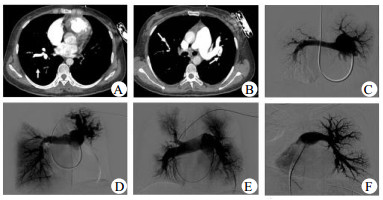

2.2 影像学和动脉受累情况CTPA和动脉造影示所有患者均肺动脉受累,且均累及双侧肺动脉。8例主肺动脉扩张,其中2例呈瘤样扩张。双侧肺动脉主干可同时受累,也可单个受累。受累血管多表现为狭窄或扩张。2例右肺动脉主干完全闭塞。每个患者均多个叶、段以及亚段肺动脉受累,表现为不同程度血管狭窄、血管壁增厚,管腔纤细、扩张、粗细不等,或动脉瘤,且DSA肺动脉造影见血管走形扭曲、僵硬,远端灌注稀疏或消失(图 1)。

| A:右中下叶肺动脉扩张,部分分支局限性狭窄,左下肺动脉未显影,提示血管完全闭塞;B:主肺动脉增宽,左侧肺动脉近段扩张、扭曲,右上肺动脉纤细,血管影稀疏;C:主肺动脉增宽,左肺动脉及分支纤细,远端灌注稀疏甚至缺失,右肺动脉远端动脉瘤,右上、中叶肺动脉僵硬,远端灌注稀疏,右下肺动脉缺如;D:肺动脉主干明显增粗,右上叶及左下叶肺动脉缺如,左上肺动脉瘤样扩张、扭曲,灌注略稀疏,右中下肺动脉近端多处狭窄,未见明显充盈缺损,远端灌注良好;E:主肺动脉和左右肺动脉增粗,右上叶前段肺动脉狭窄后闭塞,尖后段血管僵硬,远端灌注稀疏,右下叶肺动脉扩张,段肺动脉远端纤细、闭塞,灌注稀疏;左侧叶段肺动脉管腔通畅,远端灌注稍稀疏;F:左肺动脉及左侧各叶段肺动脉连续性扩张-狭窄-扩张样表现,即串珠样表现,血管僵硬,远端灌注稀疏 图 1 大动脉炎肺部累及的影像学表现 Figure 1 Images of pulmonary artery involvement in TA |

本研究患者均有肺动脉受累,累及双侧肺动脉,主干、叶、段、亚段,及远端肺动脉均有受累。CTPA表现为血管壁增厚,管腔狭窄、闭塞或扩张。肺动脉造影表现为血管迂曲、管腔僵硬、串珠样狭窄等。TA-PH与CTEPH在肺部影像学上比较相似,两者均少见,临床可能会导致误诊[11],病史和体检是两者鉴别的基本方法。CTEPH常有静脉血栓栓塞症病史,以及静脉曲张、下肢色素沉着等表现,CTPA见附壁型或中心型充盈缺损,肺动脉造影可有充盈缺损、截断征。光学相干断层成像和血管内超声等新兴技术[13]可观察血管壁形态结构,有助于两者鉴别。